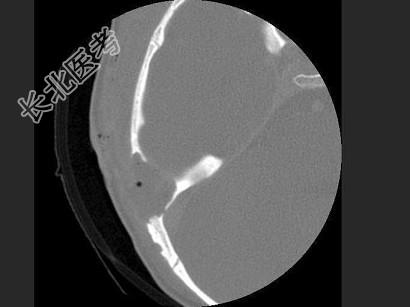

- 单项选择题女,17岁, 右耳乳突区隐痛,右耳后乳突区出现包块, 逐渐增大,CT检查如图, 最可能的诊断是 ( )

A、胆脂瘤

B、化脓性中耳炎

C、嗜酸性肉芽肿

D、中耳癌

E、听神经瘤